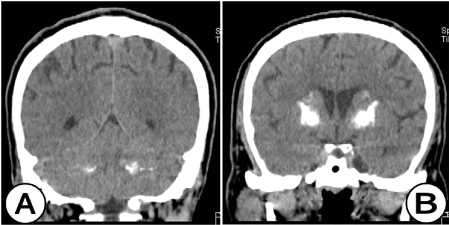

Рис. 5. Нативная КТ  головного мозга (корональная плоскость). (А) На уровне задней черепной ямки отчетливо видны двусторонние, высокоплотные и обширные участки кальцификации с вовлечением зубчатых ядер и гемисфер мозжечка. (Б) На уровне передних рогов боковых желудочков на КТ визуализируются аналогичные зоны кальцификации в базальных ганглиях (хвостатое ядро, бледный шар, чечевицеобразное ядро ​​и скорлупа) у мужчины 56 лет.